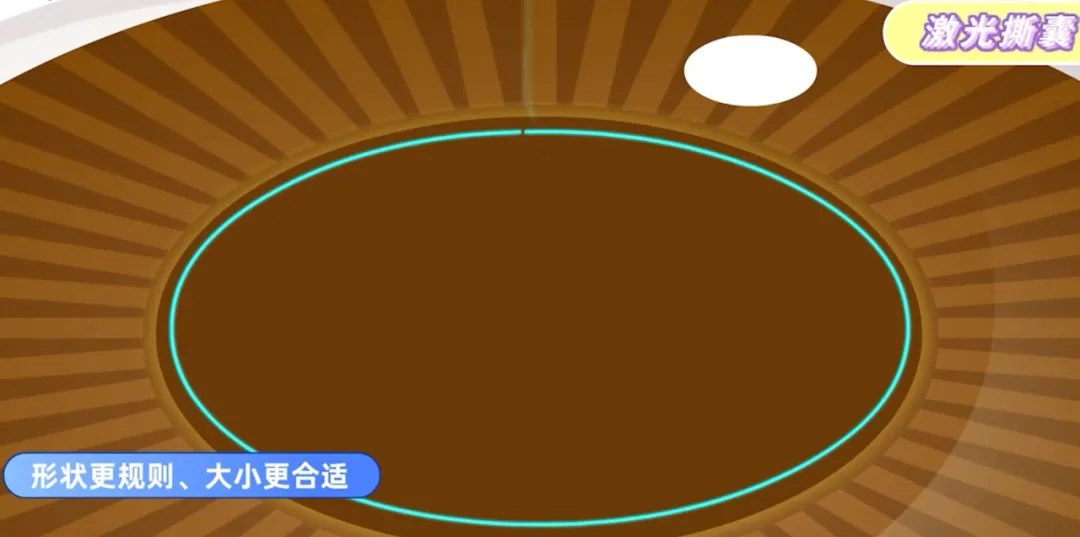

针对硬核,膨胀期,过熟期白内障、先天性白内障、年轻人白内障以及糖尿病白内障患者,相比传统手术,飞秒激光白内障手术更有优势。

传统的白内障手术,在超声乳化的关键步骤制造切口和撕囊时,都是依靠医生手动操作。所以,医生的经验和技巧非常重要,切口会影响恢复速度和术后视力,容易产生机械变形和渗透,而手工撕囊的质量影响术后并发症和视觉质量。

随着技术发展,以飞秒激光辅助白内障手术技术为代表的,前沿手术方式正受到越来越多人的青睐。

飞秒激光可以代替医生的手工切口,预先分割囊膜内的混浊晶体,整个过程都有电脑扫描成像技术辅助,可以准确地制造切口并撕囊,使其光滑平整,还可以利用飞秒激光去除患者部分散光问题,再用超声波去除晶体。